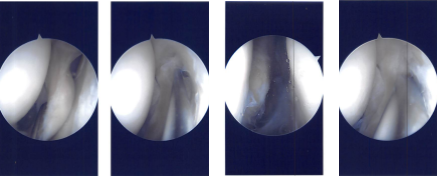

There was a small patch of grade 2 to grade 3 arthritis on the medial patellar area, which was cleaned. Examination of intercondylar notch was intact ACL. Examination of the tibiofemoral joint medial marginal meniscus, which was cleaned using shaver and upbiters. There was no tear in the medial meniscus.

There was a large popliteal hiatus with the possible tear going into the posterior horn of the lateral meniscus, which was incomplete. A thorough examination was done, and the debridement was done. The decision was made not to repair it at present because it seemed to be an extensional popliteal hiatus.

Intraoperative Arthroscopy Images